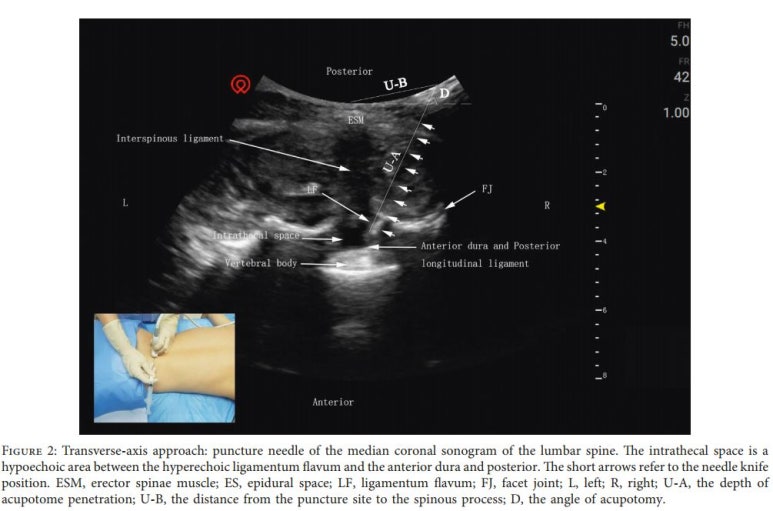

횡축으로 접근시 (가로)

프로브를 L4 극돌기에 종축방향으로 두고 약간 아래쪽으로 이동하면, L4와 L5극돌기 중간선을 확인한 뒤 프로브를 90도 돌립니다.

시술 포인트는 프로브와 가깝고 바늘이 가장 짧게 들어가는 경로를 찾습니다.

그러나 종축 접근에 비해횡축 접근시 시술의 깊이가 더 얕았기 때문에 임상에서는 횡축 접근을 하는 것이 더 안전하다고 보고하였고, 횡축 접근이 접근 각도가 더 크기 때문에 선명한 이미지를 만들 수 있었습니다.**

위 그림과 같이 바늘 끝이 뼈 표면에 위치하여 시술해야하며, 바늘이 더 깊숙하게 떨어지는 느낌이 든다면 척수경막을 뚫을 수 있으니 깊이 들어가지 않아야 합니다.**